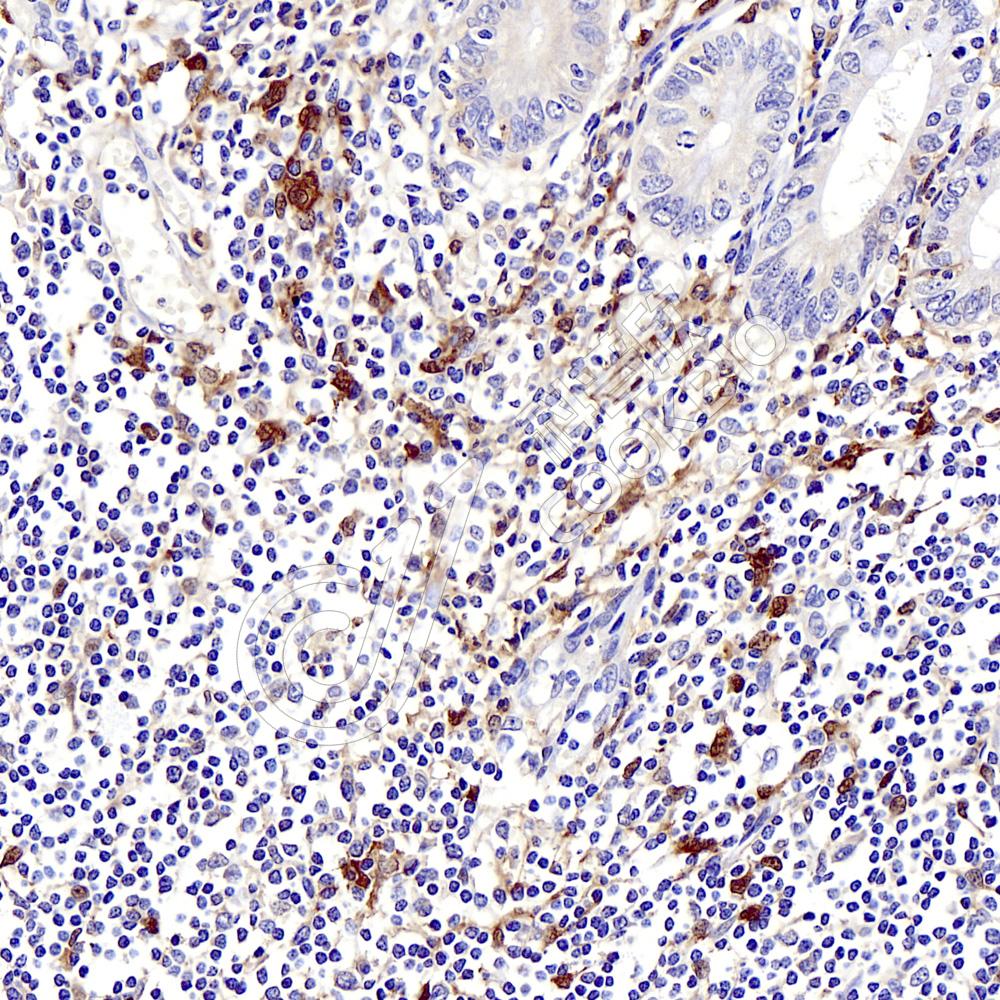

IHC检测NK-p44蛋白(货号 K134845).

样品: 人阑尾, 4%多聚甲醛 (货号KSG1101) 固定12-24小时.

抗原修复: 柠檬酸抗原修复液(干粉, pH 6.0) (KSG1201), 98℃, 20分钟.

—抗: 1: 600稀释, 4℃ 孵育过夜.

二抗: S-vision免疫组化多聚二抗(山羊抗兔),即用型 (货号KB3906), 室温孵育20分钟.

样品: 小鼠脾, 4%多聚甲醛 (货号KSG1101) 固定12-24小时.